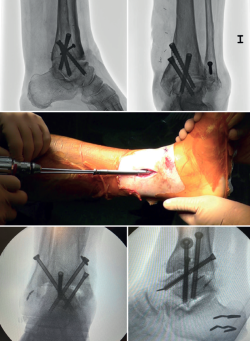

In arthroscopic ankle arthrodesis, the use of percutaneously placed compression screws is the technique of choice (Figure 5).

Most authors consider the use of cannulated screws (3 to 4) to be the ideal fixation method. The diameters of the chosen screws should be between 6 and 7 mm. This technique achieves 85-100% fusion and 84-95% patient satisfaction rates(19).

Van Dijk, Kerkhoffs et al.(20) reported excellent results with the use of three screws as the standardized method for ankle arthrodesis.

Screw configuration and placement

Depending on the deformity involved and according to preoperative planning, screw placement is carried out starting with the compression screw that counteracts the deformity.

In other words, in arthropathies with a varus component, we would start with a lateral screw, while in valgus misalignments the recommendation is to place the first screw from the medial side. The second screw should be on the side opposite to the first. Both should provide adequate compression between the joint surfaces(17).

In general, a minimum of three screws are used. The third screw is the so-called home run screw, the importance of which has been highlighted by Holt et al.(21). It is directed across the ankle from the posterior part of the tibia to the neck of the talus. A fourth screw may be used as an augmentation of the first, counteracting the main deformity.

Goetzmann et al.(22), in their review of 111 cases, supported the use of at least three screws for fixation of arthroscopic tibiotalar arthrodesis. The addition of a third screw appears to be associated with a lower risk of pseudarthrosis and shorter consolidation time. These effects can be attributed to an increased stability of the construct.

Glick, Myerson(23) et al. reported that the configuration conferring the greatest rigidity to the osteosynthesis comprises two screws from medial and one from the lateral side.

In cases where there is anterior translation of the talus, good resection of the posterior tibial malleolus is important to allow for reduction and proper positioning of the talus. Another useful technique is, in the supine position, to place a support under the distal tibia leaving the heel free to be manually moved posteriorly.

In some of these cases with anterior translation of the talus, and contrary to the usual recommendations, it may be useful to first position the posteroanterior screw with partial threading, to reduce the talus from anterior to posterior and align it with the lateral longitudinal axis.

Definitive anteroposterior, mortise, lateral ankle, dorsoplantar and oblique foot radiographs are obtained to confirm correct reduction, and the position and length of the screws, especially the home run screw (Table 3).